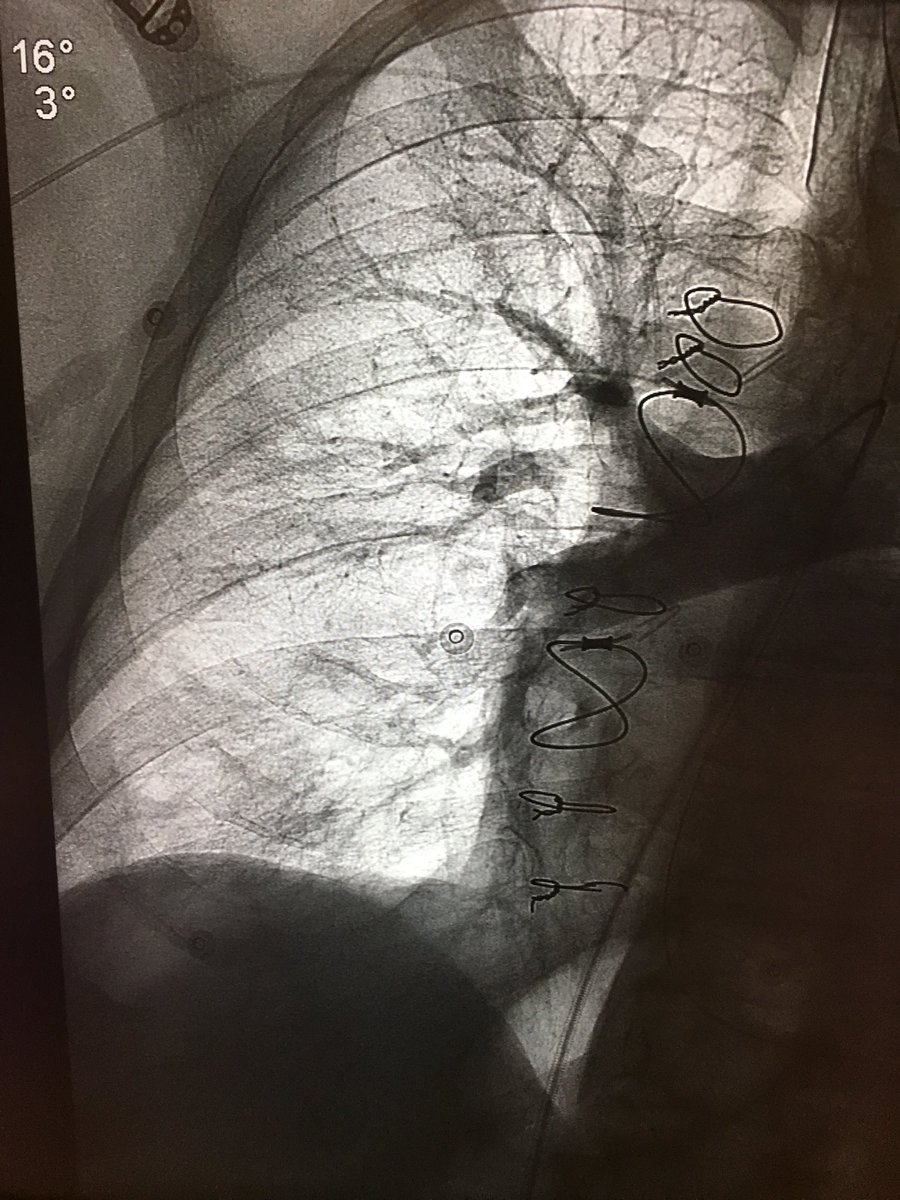

47 yo p/w massive PE s/p systemic tPA and persistent hypotension. Extensive right-sided PE on angio. Thrombus completely removed with FlowTriever mechanical thrombectomy. PA pressure decreased to 30mmHg from 64 mmHg immediately. #IRad @SIRspecialists @SIRRFS @SIR_ECS @JVIRmedia